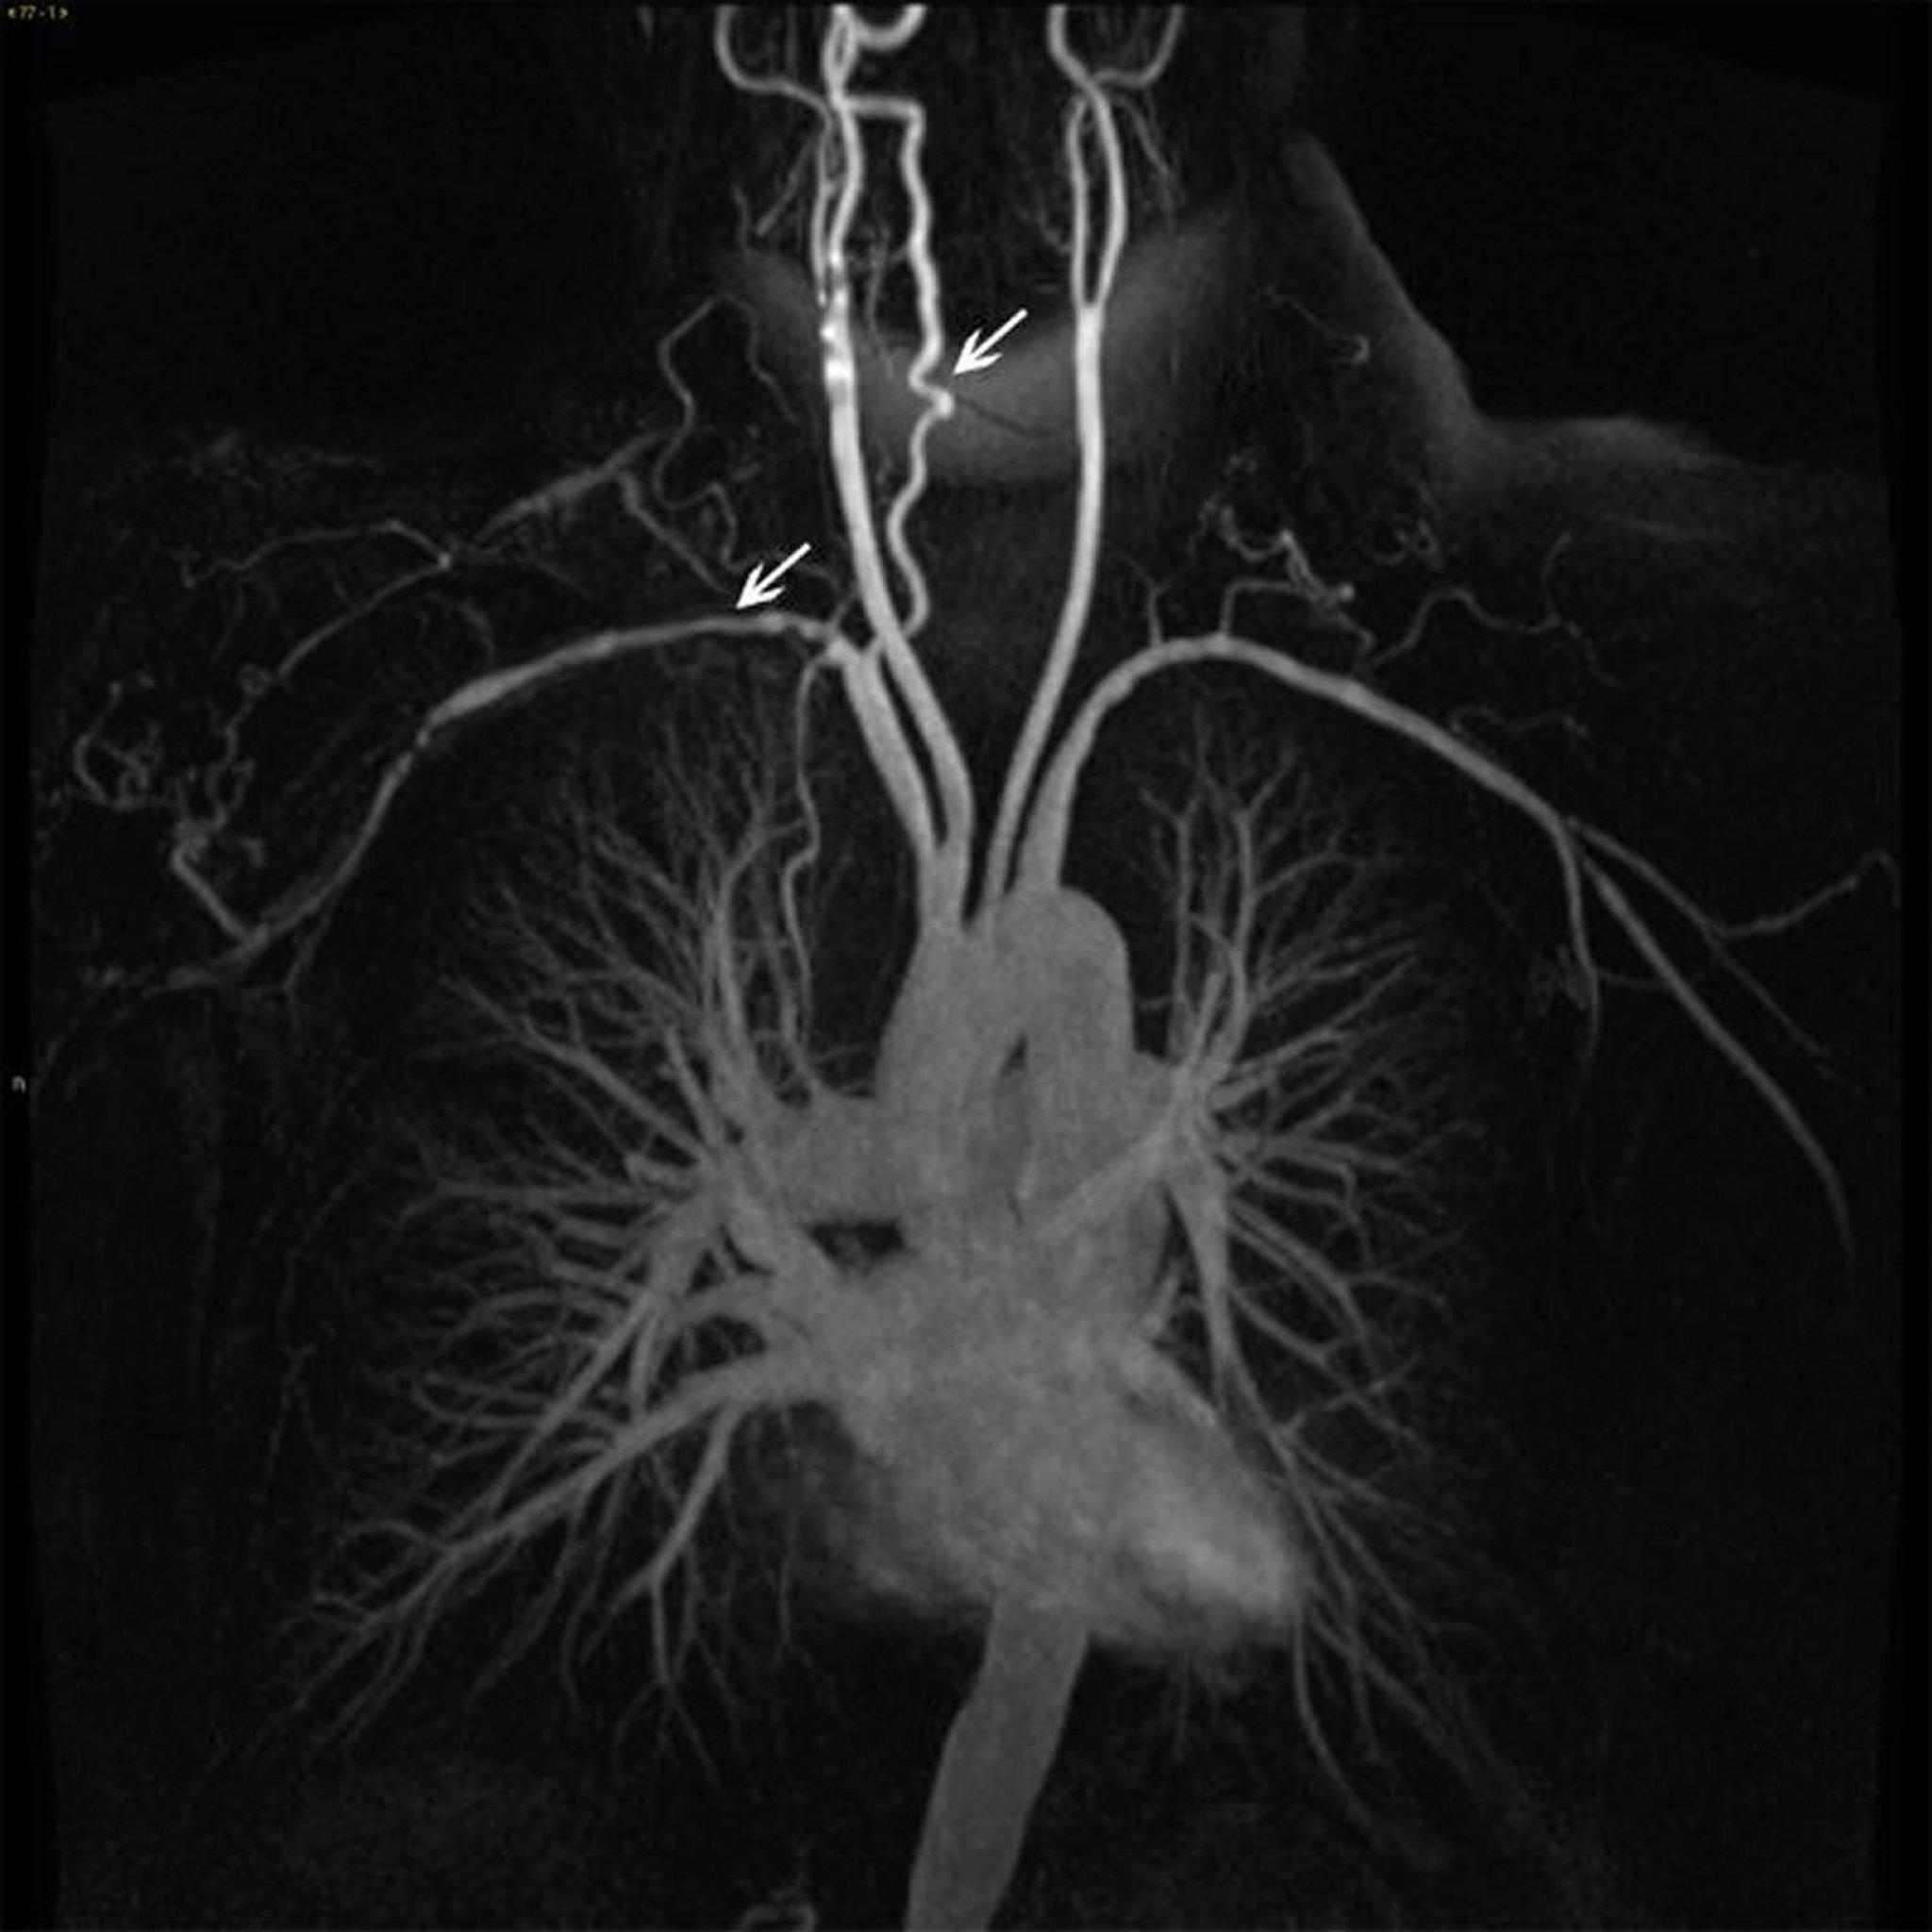

Ветви восходящей части грудной аорты у пациента с артериитом Такаясу

Это изображение показывает неровности и сужение стенки (белые стрелки) в нескольких ветвях восходящей аорты.